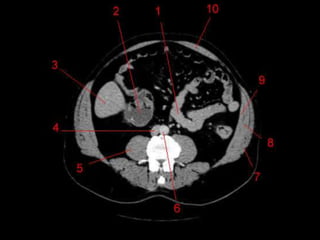

• TC: Tres fases

– Arterial (10 a 20 segundos)

– Fase venosa portal ( 30 segundos )

– Fase venosa hepática (60 segundos)

Técnicas de Imagem •US: Primeiro exame pedido ao: 1) dor no hipocondrio direito; 2) testes de função hepáticas anormais; 3) suspeita de malignidade. • TC: Tres fases – Arterial (10 a 20 segundos) – Fase venosa portal ( 30 segundos ) – Fase venosa hepática (60 segundos) • TC Portografia: Metastases.